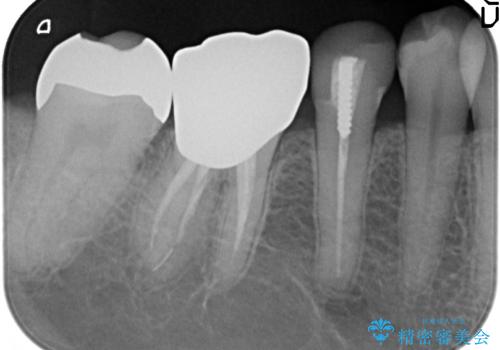

- 冷たいものを飲むと右下の奥歯が痛むので診て欲しいといらっしゃった方の症例です。

銀歯及び虫歯を除去後、より適合の良いPGA(ゴールド)インレーによる修復を行いました。

- PGA(ゴールド)インレー…¥60,000費用は治療当時の料金となります